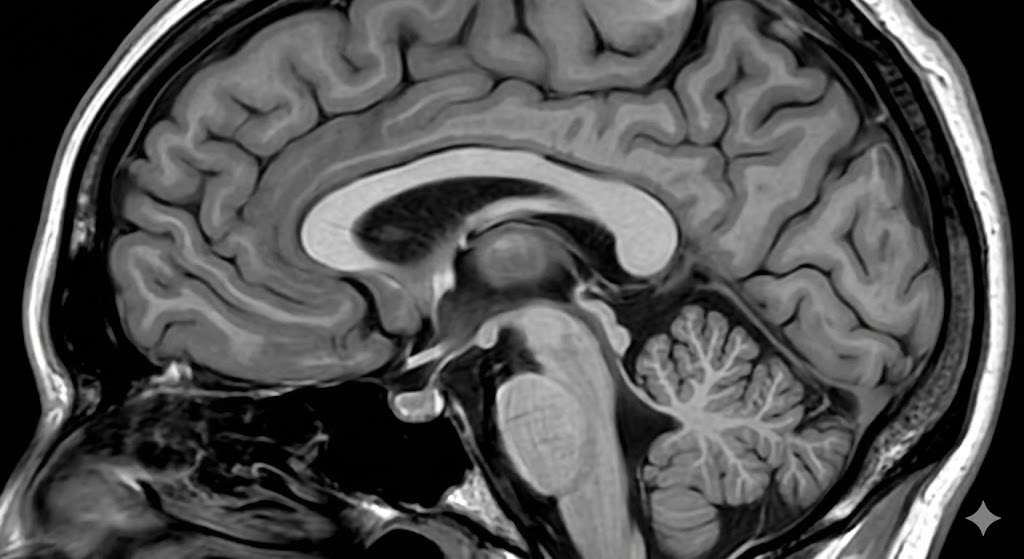

이런 걱정이 들 때 가장 먼저 떠오르는 것이 바로 MRI 검사입니다. 하지만 선뜻 병원을 찾지 못하는 이유는 바로 '비용' 때문이죠. 병원마다 가격이 천차만별이고, 비급여로 찍으면 100만 원이 훌쩍 넘는다는 소리에 망설이게 됩니다.

하지만 걱정하지 마세요. 증상에 따라 조건만 맞으면 건강보험이 적용되어 10만 원대에도 검사가 가능합니다. 오늘은 2026년 기준 병원급별 MRI 가격 차이와 보험 적용 기준, 그리고 실비 보험 100% 활용 꿀팁까지 정리해 드립니다.

1. 병원급별 뇌 MRI 평균 가격 (왜 가격이 다를까?)

결론부터 말씀드리면 아닙니다. 가격 차이의 핵심은 **'장비의 해상도(테슬라, T)'**와 **'병원의 규모'**에 있습니다.